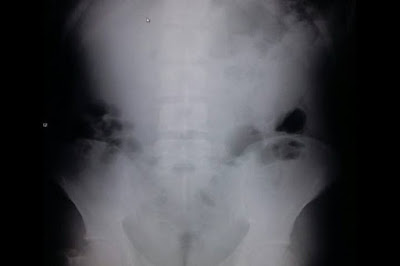

Ao realizar a operação Carrossel de Fogo no final da tarde desta quinta-feira (12) no bairro Borja, a GT ordinária foi

informada de que o imputado [F V F A] de 18 anos, solteiro, estudante tinha comprado ao imputado [D D O S] de 20 anos, amasiado, agricultor uma porção da

substância entorpecente conhecida como “maconha”. O policiamento seguiu

para o local, identificou o 1º imputado que ao avistar a viatura engoliu

uma parte da droga, porém uma pequena quantidade ainda foi encontrada